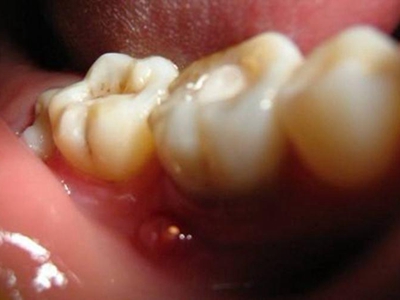

牙龈

化脓

智齿冠周炎智齿周围牙龈脓肿图

智齿冠周炎患者可出现磨牙后区疼痛,检查可见智齿萌出不全,周围牙龈肿胀,部分患者可有脓肿形成,白色的脓液可从牙周袋内溢出。